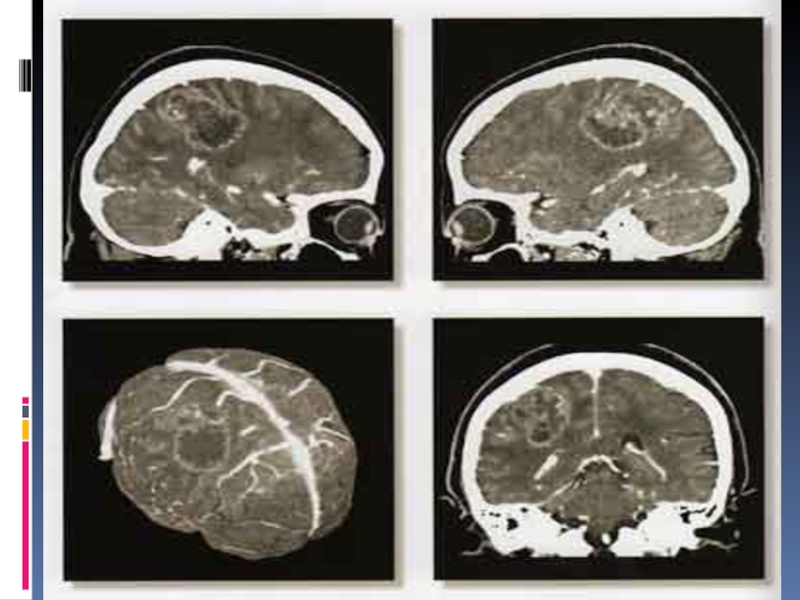

Слайд 37Компьютерная томография

Позволяет визуализировать особенности строения мозга человека с помощью компьютера

и рентгеновской установки

Источник рентгеновских лучей вращается в одной плоскости вокруг

головы, рентгеновские детекторы постоянно регистрируют интенсивность проходящего сквозь голову излучения, компьютер преобразует полученные данные в рисунки срезов мозга различной глубины

Толщина срезов не более 5 мм

Для улучшения качества изображения перед исследованием пациенту вводят контрастное вещество, например, верографин (содержит йод)

Эффективна при диагностике инсультов, рассеянного склероза, опухолей

Компьютерная томографияПозволяет визуализировать особенности строения мозга человека с помощью компьютера и рентгеновской установкиИсточник рентгеновских лучей вращается в

Слайд 38Компьютерная томография

Компьютерная томография